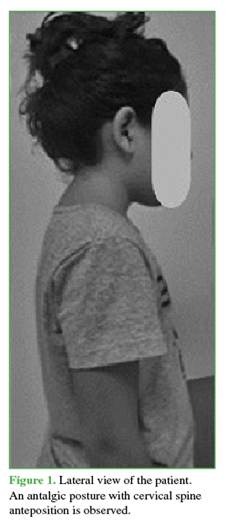

A 9-year-old girl presented with chronic pain (>2 years) in the lower cervical and interscapular region. She denied any relevant personal or family medical history. On questioning, she reported upper back pain that did not respond to pharmacological or physical therapy.

Physical examination revealed gait disturbance with a widened base of support, bilateral patellar hyperreflexia, and paresis corresponding to the right C7 nerve root. This was manifested as weakness in the right triceps muscle (grade 4/5), as well as in the wrist flexors and extensors on the right side (grade 4/5), according to the Medical Research Council (MRC) muscle strength scale (Figure 1).10